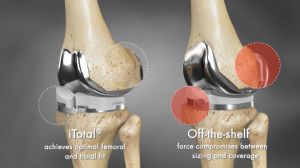

Surgeons usually have no choice but to adjust implant rotation, alignment, and fit because off-the-shelf implants are not engineered to patients’ varied anatomy. This is why some patients experience sustained pain after the surgery and why 1 out of 5 aren’t happy with their knee implants.

Our partner, Conformis, wanted to address this issue by developing knee implants for every one of our patients. Their aim for this groundbreaking technology is to give you a pain-free lifestyle by helping you recover your natural motion so you can return to your regular activities. These custom-made knee implants are built distinctly for your particular anatomy, providing the best results in knee replacement surgery.